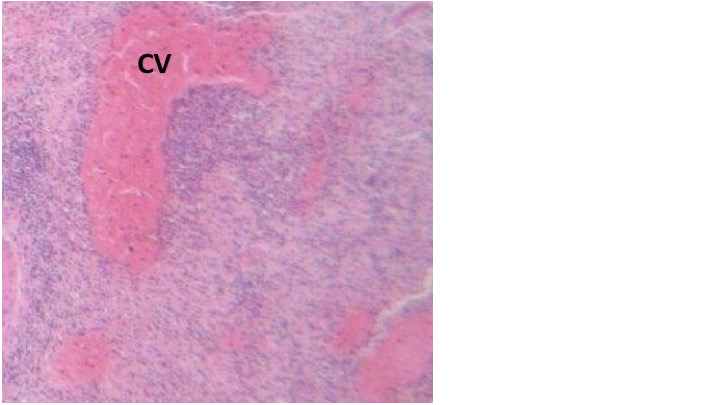

El Síndrome Compartimental Abdominal (SCA) y la Hipertensión Intraabdominal (HIA) son conocidos desde los estudios tempranos del Siglo XIX en Francia, como entidades patológicas que ponen en riesgo la vida derivado de graves eventos deletéreos afectando las extremidades o el abdomen, estructuras bien delimitadas por las fascias o bien cavidades óseas que inesperadamente sufren un aumento drástico de su presión interna. El objetivo de este trabajo fue investigar las notables analogías morfofisiopatológicas que caracterizan a esta condición, y correlacionarlas como base diagnóstica contra dos casos clínicos espontáneos de SCA observados en cerdos híbridos de la raza Landrace-Yorkshire de 5 meses de edad, que posterior a sus intervenciones quirúrgicas muriesen en forma hiperaguda por asfixia con datos de tipo Síndrome Policompartimental (SPC).   A la inspección clínica inicial se observó eritema facial diseminado, extensa hemorragia subconjuntival, epistaxis, marcada distensión abdominal con dehiscencia de la herida quirúrgica previa y evisceración masiva en un caso, así como moderada en el segundo animal, presentando ambos sujetos prolapso rectal y aparente necrosis de mucosa. Los hallazgos de histopatología revelaron cambios multiorgánicos focales pero graves afectando órganos internos con isquemia, dilatación y congestión. Se postula que debido a la asfixia repentina y la naturaleza hiperaguda de las lesiones encontradas, ello explica una disfunción multiorgánica circunspecta consistente con hallazgos de casos descritos de SPC tanto en modelos animales inducidos como en casos graves de eventualidades humanas. Finalmente, se postula que esta investigación analógica ilustró cómo un caso espontáneo de SPC cumplió con criterios diagnósticos internacionalmente aceptados para esta condición humana, representando en el caso del cerdo un modelo animal inducido asequible que permitirá enriquecer la investigación del SPC, una rareza que a nuestro juicio nunca se había reportado como ocurrencia espontánea en un animal de laboratorio.